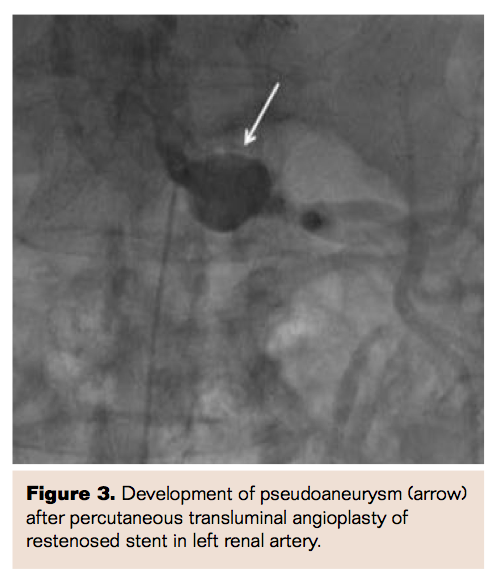

The patient had been aggressively managed for hypertension and for ischemic heart disease. Bilateral renal artery stenosis intervention had been performed, with bilateral proximal renal artery stents (6 mm x 18 mm, Medtronic stents) placed approximately 1 year prior to presentation. The patient had an angioplasty (6 mm x 20 mm balloon catheter) of left renal artery 8 months later for restenosis within the stent (Figure 1).